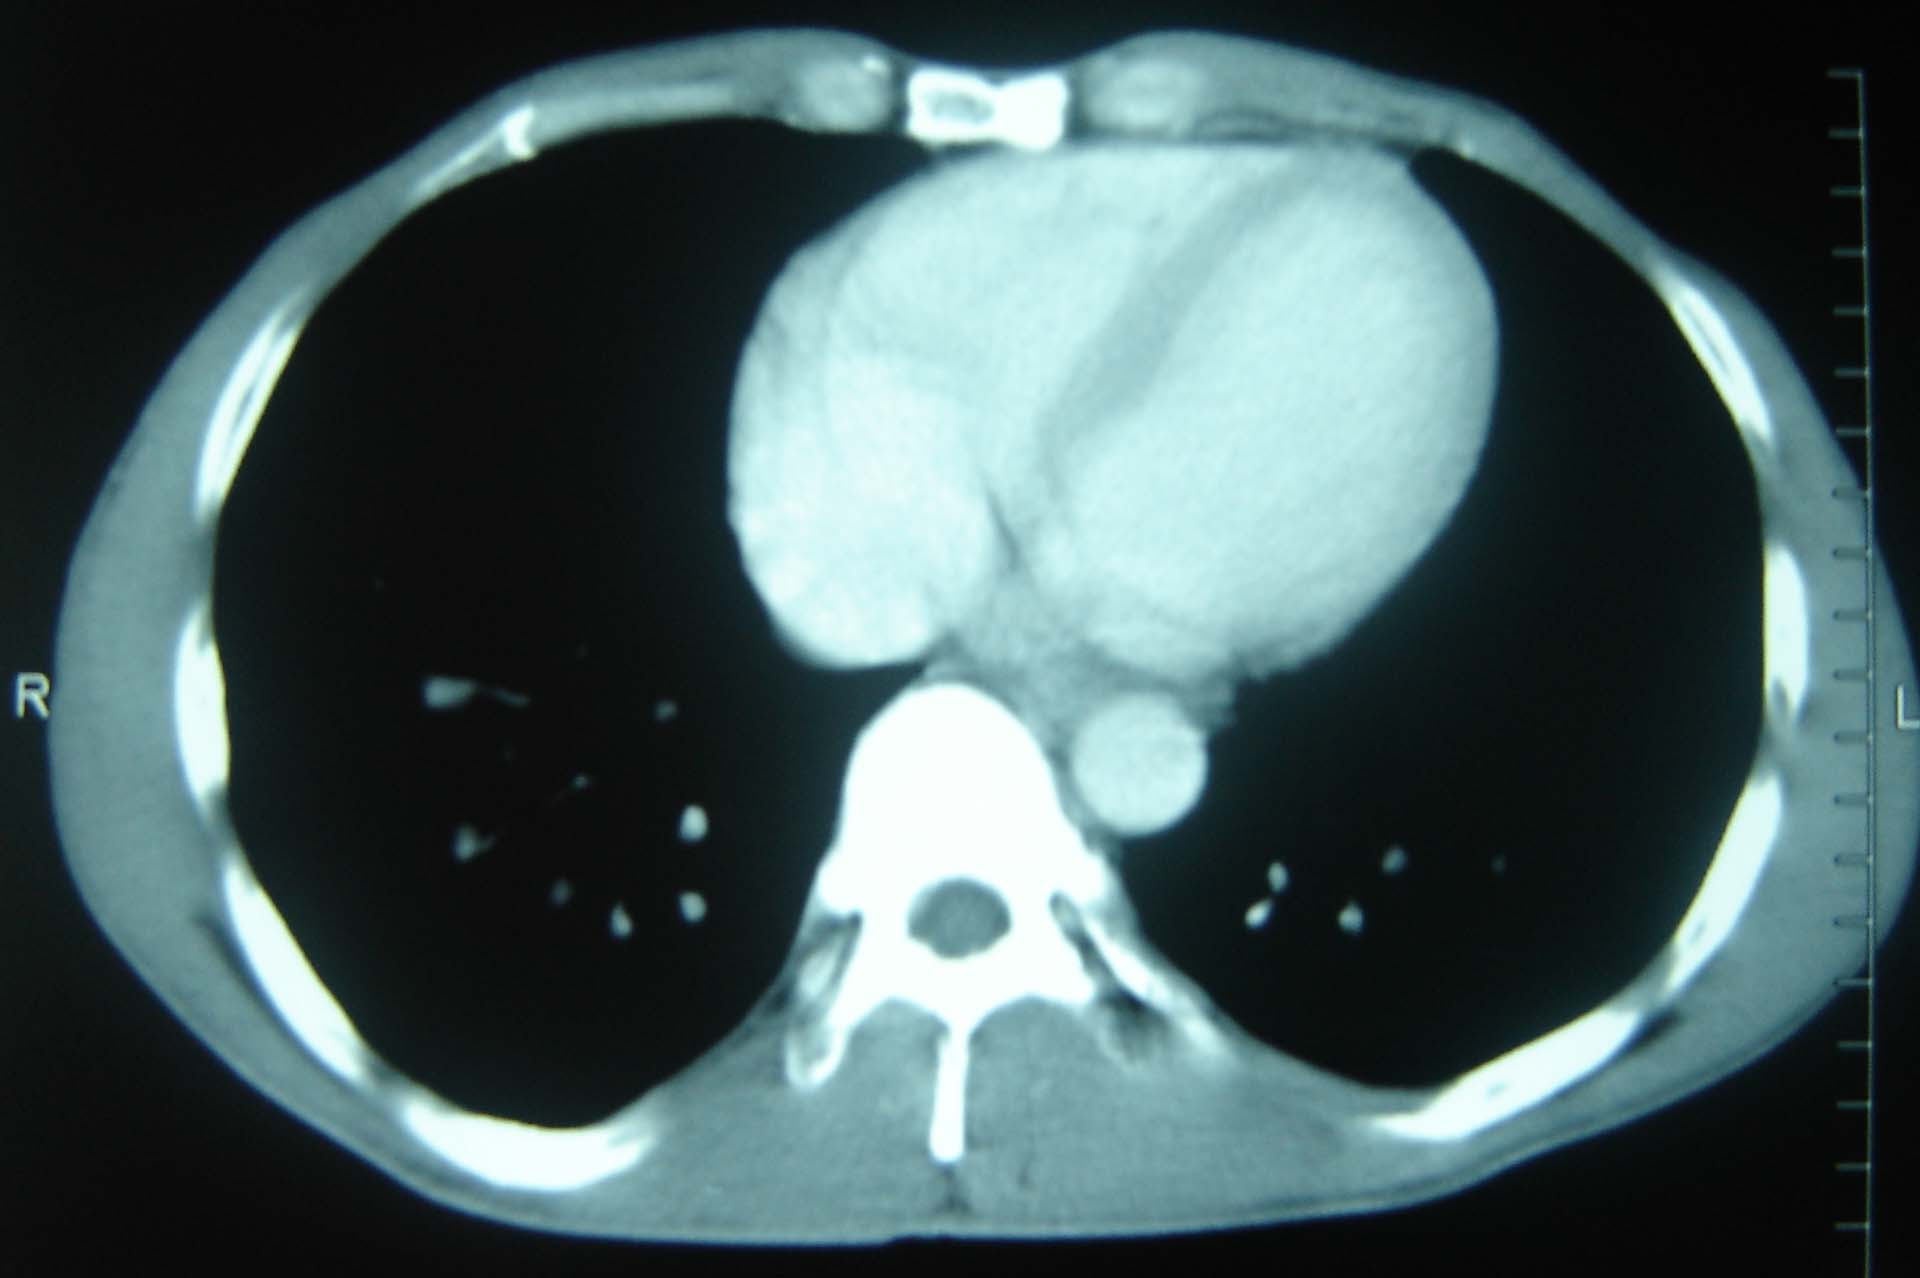

标题: CT25321:两肺多发结节 请会诊 [打印本页]

男 、43岁,咳嗽胸痛,装修工,平时接触粉尘较多,有吸烟史10多年,纤维支气管镜检查未发现异常,胃镜、腹部b超检查亦未发现异常,颈部淋巴结活检未发现肿瘤细胞。